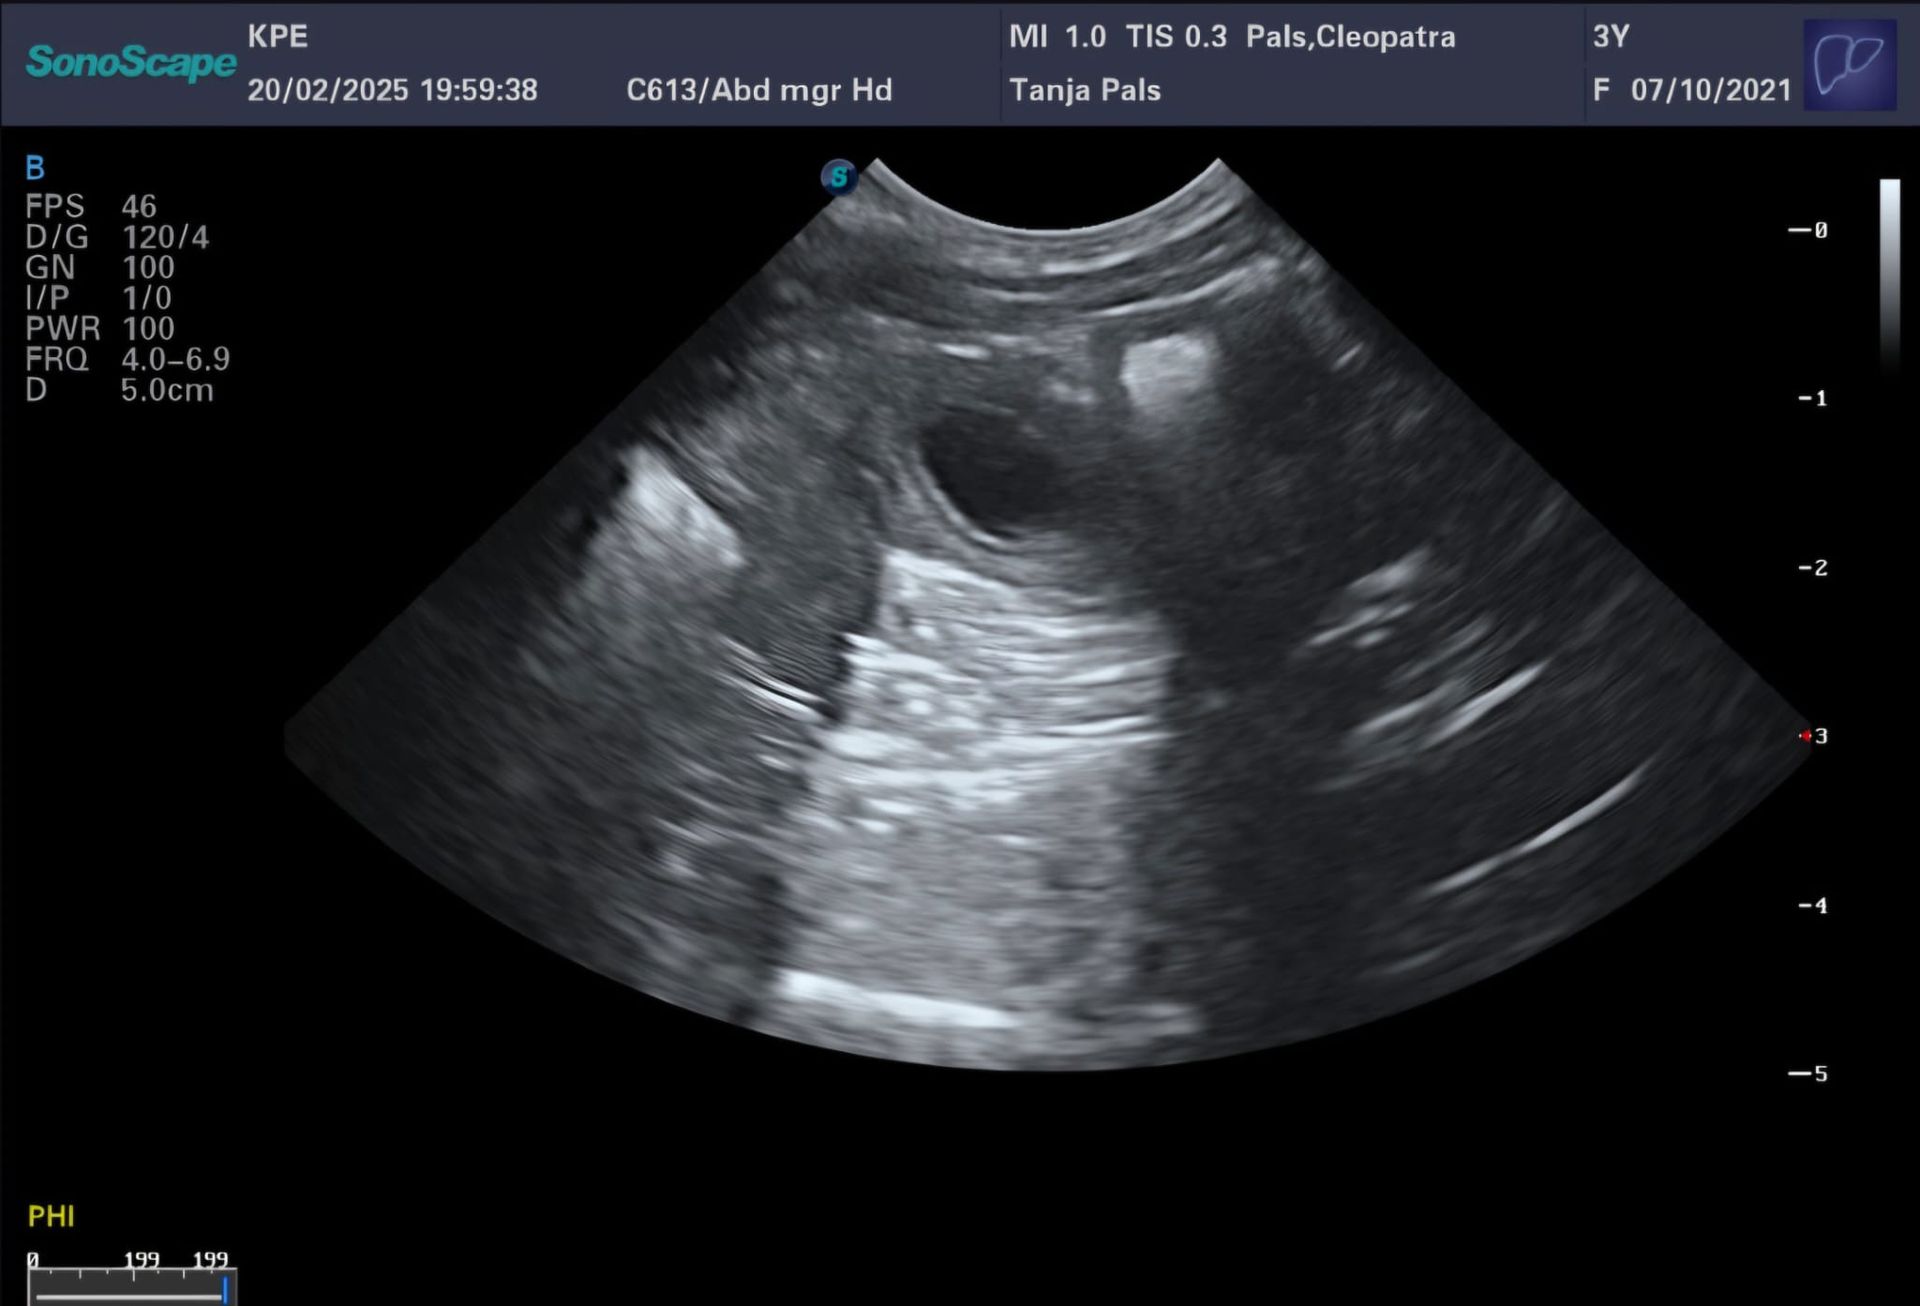

20.02.2025 schon der 24.Tag von etwa 63. Die Ultraschalluntersuchung zeigt es gibt gut erkennbare Fruchthüllen. Cleopatras Herz schlägt kräftig. Der Puls ist super. Cleopatra zeigt eine erhöhte Durchblutung. Super Voraussetzung um die Embryos fest in der Gebärmutter aufzunehmen. Wir sind sehr glücklich, da wir jetzt wirklich trächtig sind.